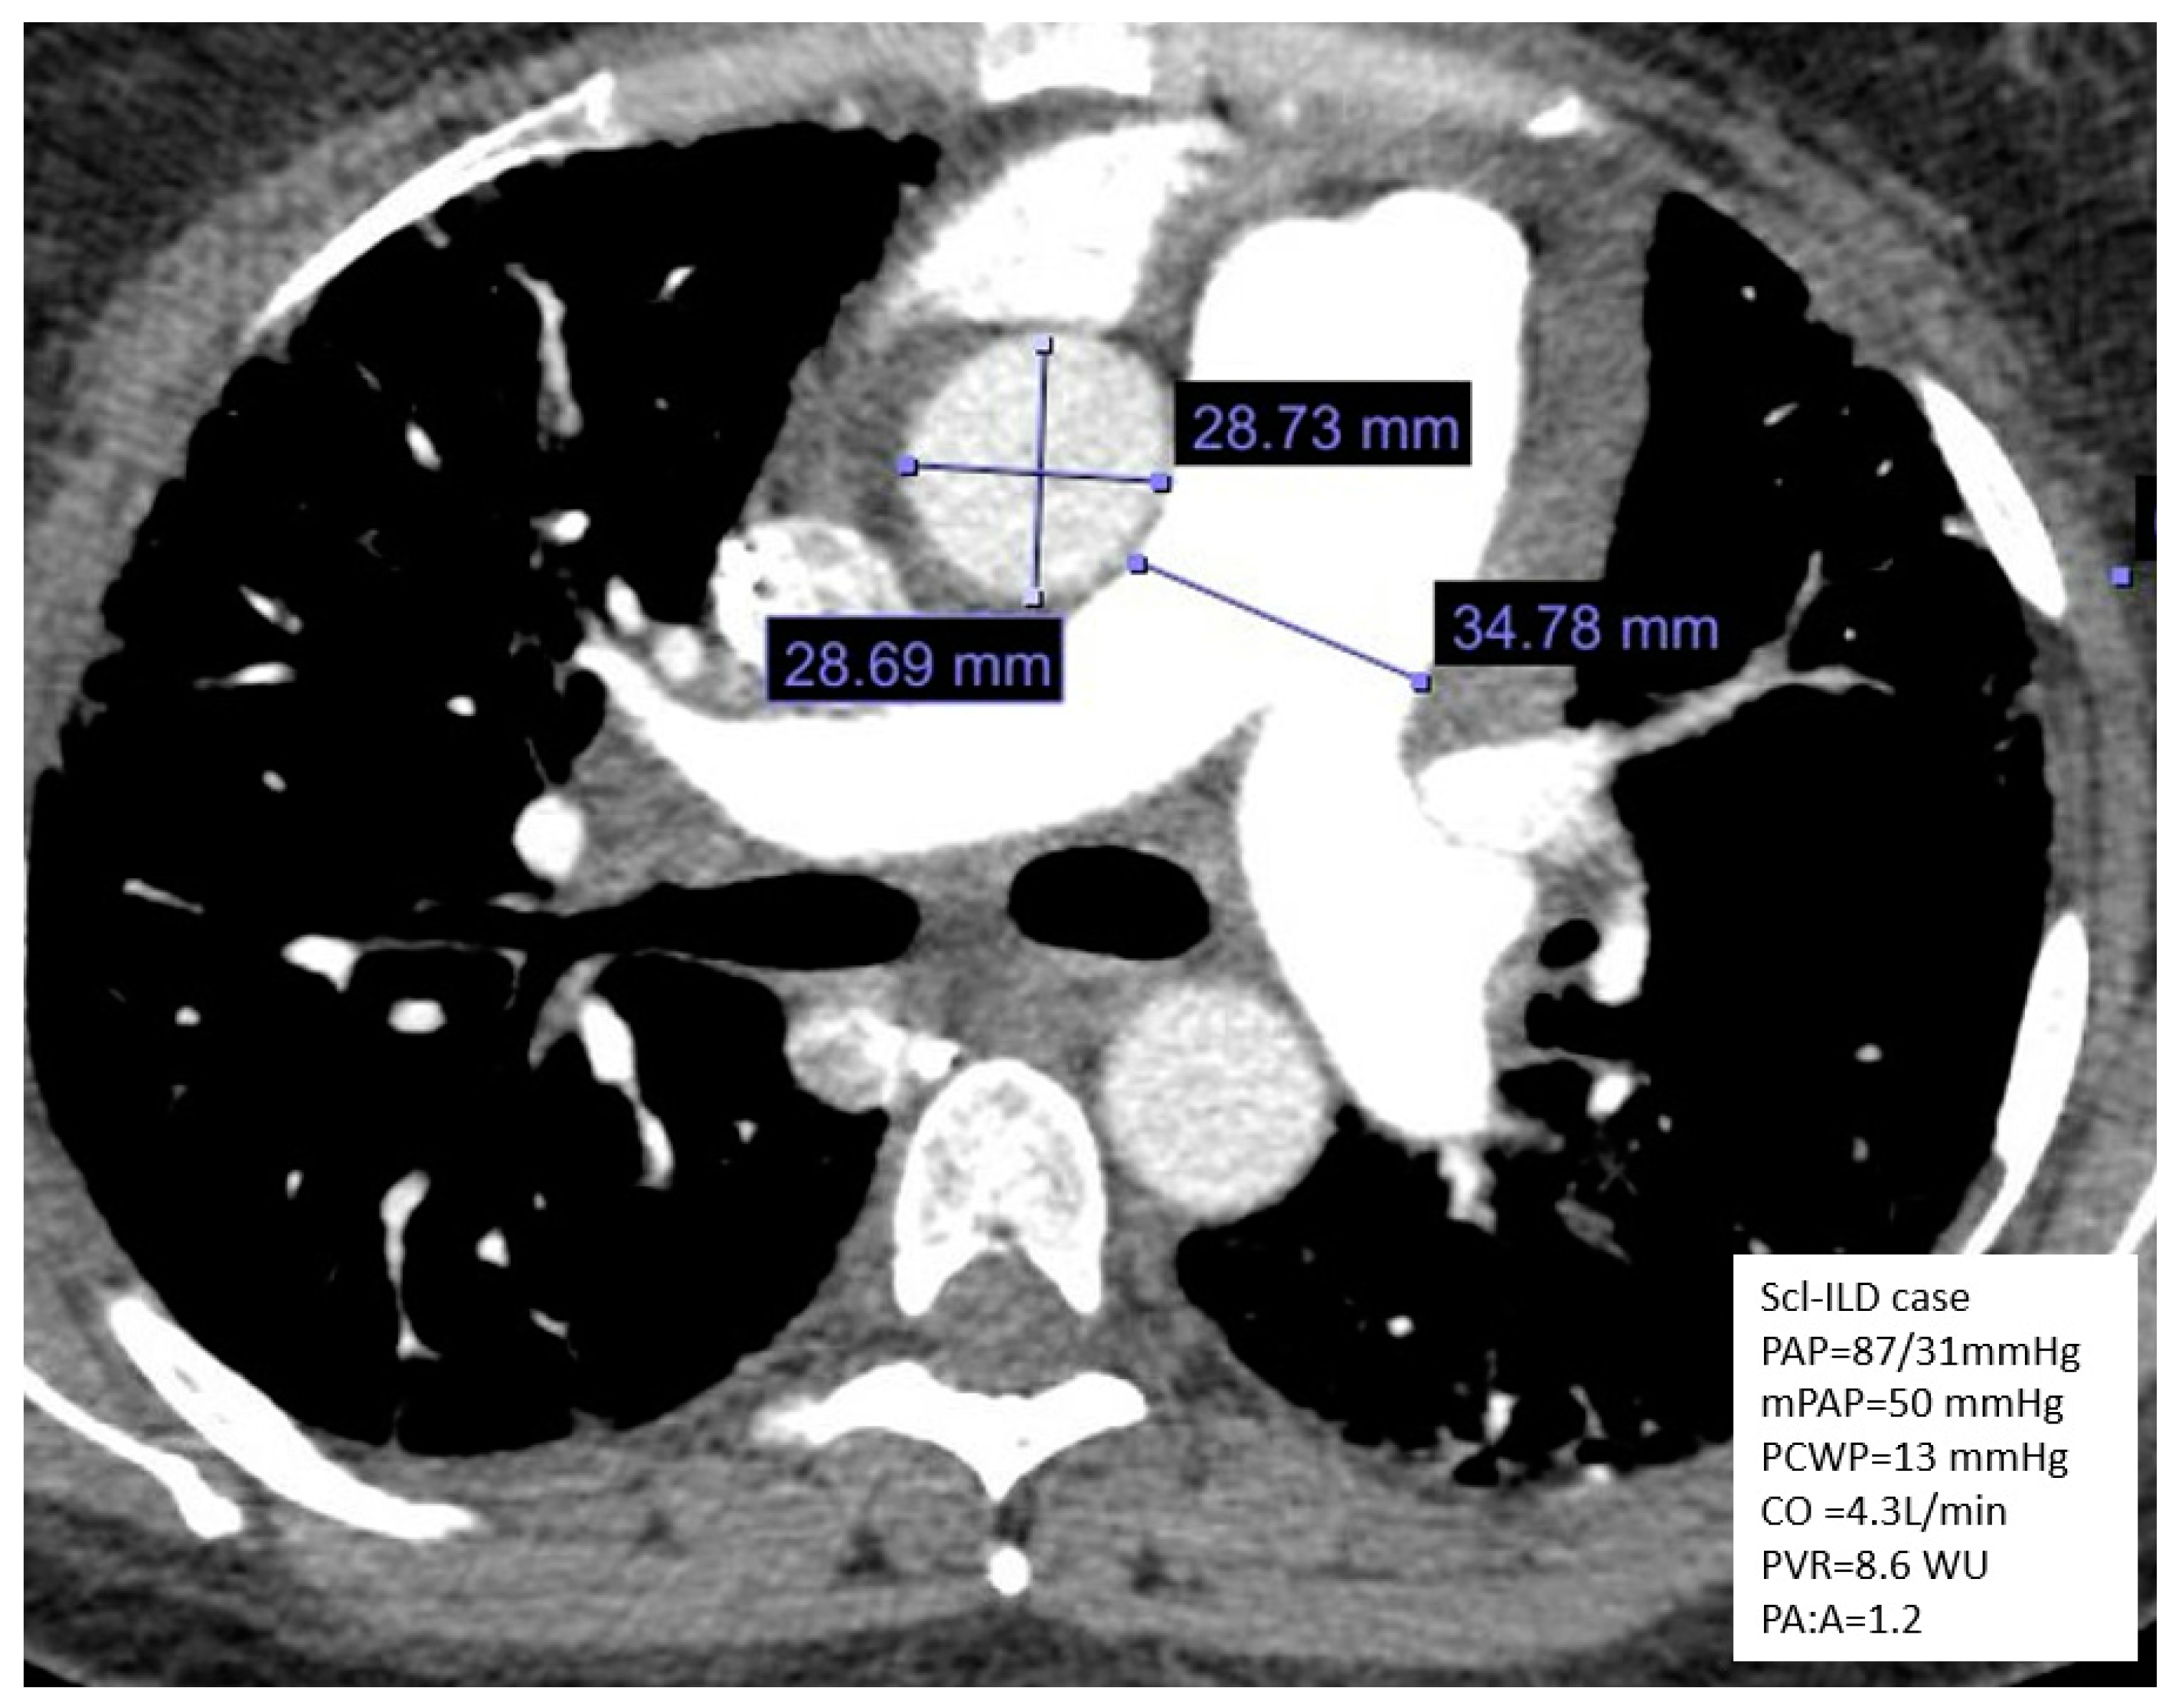

5.5. CT Imaging